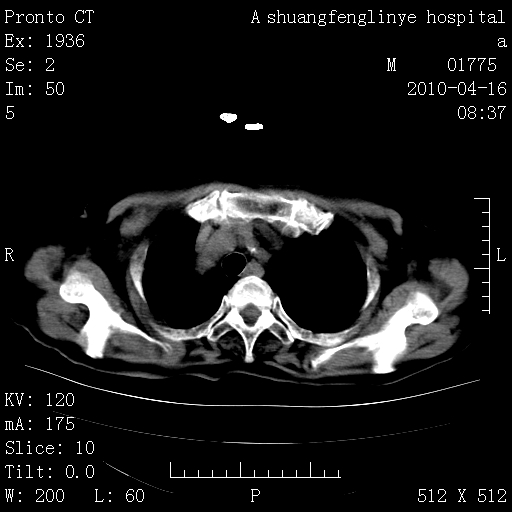

老年肺间质纤维化,肺动脉高压-----肺心病。

慢支肺气肿,左上陈旧性结核,主动脉冠脉钙化

1)左肺上叶结核(纤维、增殖病灶)。2)冠状动脉及主动脉钙化。

1)左肺上叶结核(纤维、增殖病灶)。2)冠状动脉及主动脉钙化。肺动脉高压